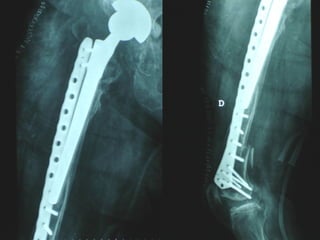

INDICAZIONI COMUNI Fratture sovracondiloidee Fratture intercondiliodee Fratture diafisarie distali PARTICOLARI Fratture con grave osteoporosi Fratture periprotesiche

VANTAGGI CHIRURGIA MININVASIVA Mini Open Inserimento della placca sottocutaneo per scivolamento Viti percutanee Preservazione dei tessuti molli Ridotto danno vascolare Rapida ripresa funzionale

LISS  NCB

NCB

Conclusioni Riduzione  anatomica Minimo trauma chirurgico Corretto equilibrio fra elasticità e stabilità Precoce mobilizzazione